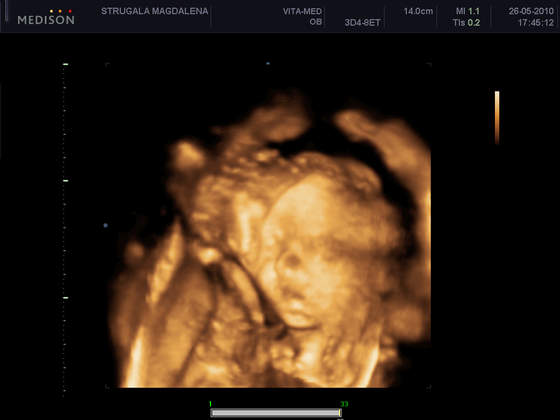

co do 4D jeszcze nie bylam, dzwonilam w dwa miejsca i na walbrzyskiej wlasnie u wrobla, robią dopiero po 28tc

a tam kolo zusu- podhcorążych- już moglbym isc- 200zł + 50zł za opis jak się chce